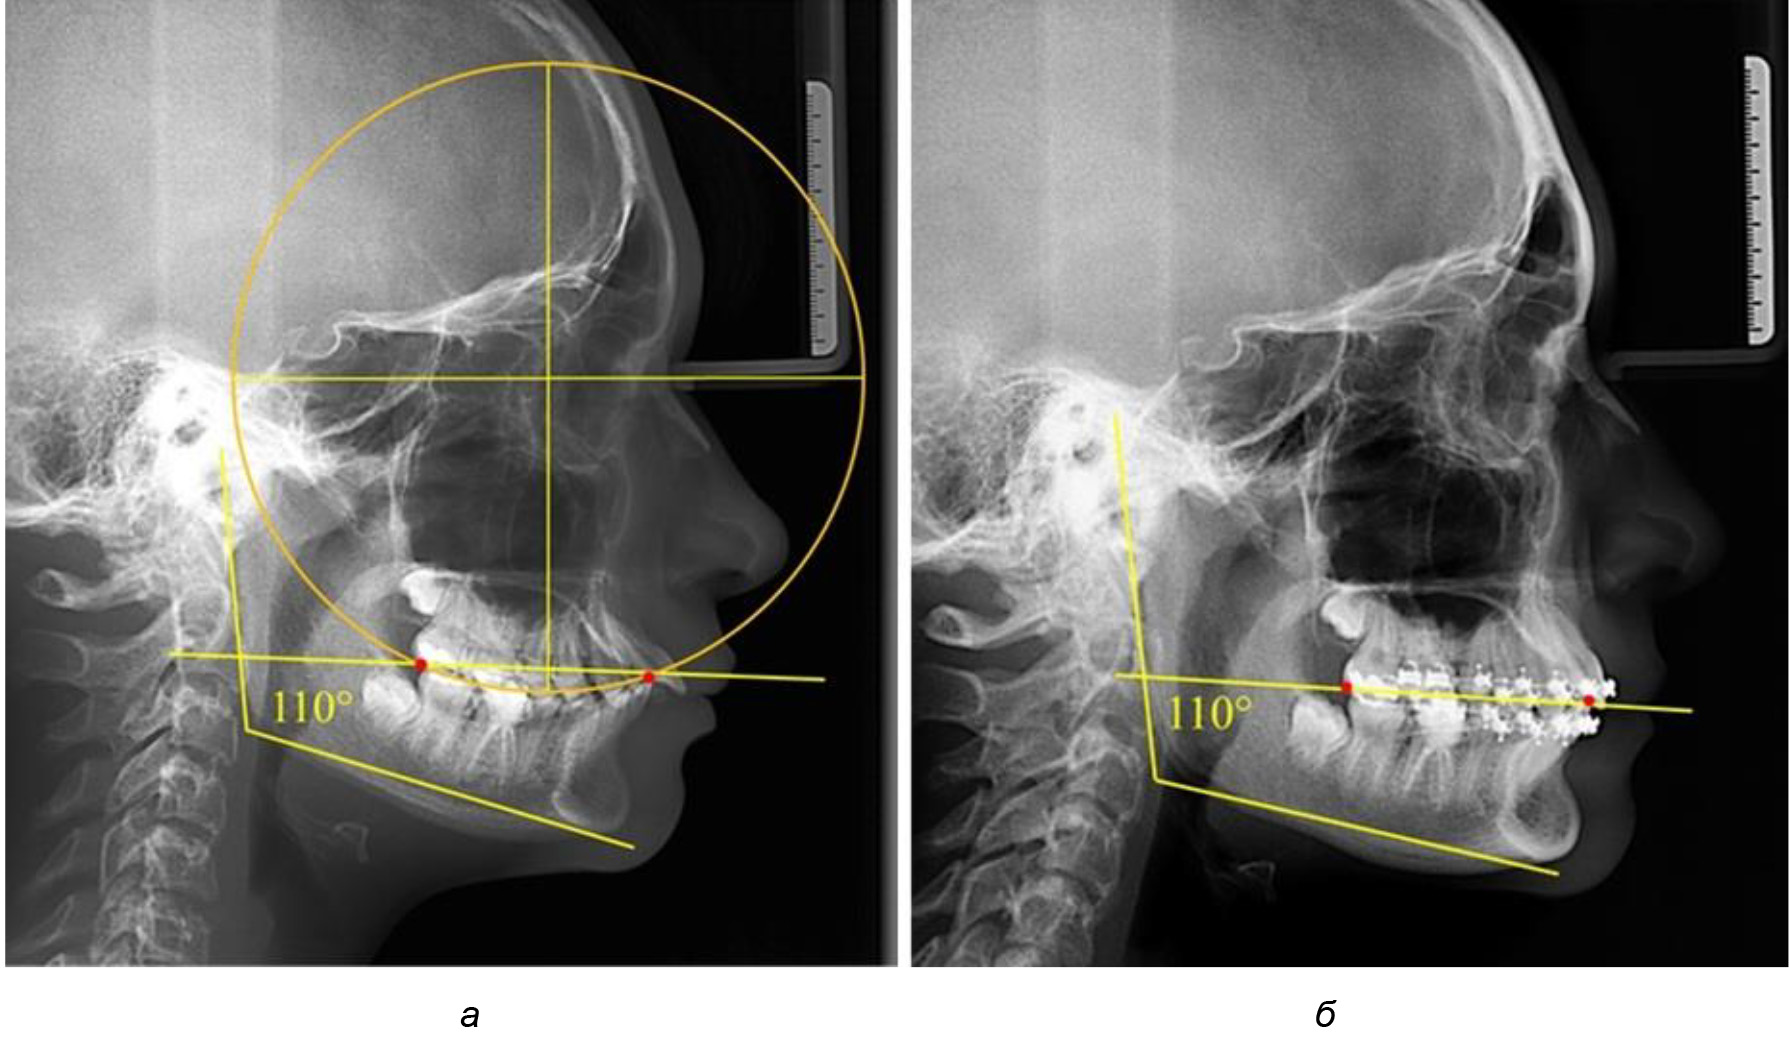

В ходе исследования установлено, что в 1-й подгруппу вошли ТРГ и ОПТГ 18 человек 1-й группы, что составило (29,03 ± 5,78) % от всех пациентов, рентгенограммы которых были проанализированы. У всех пациентов величина угла нижней челюсти была более 125° и в среднем составила (129,89 ± 3,62)° и характеризовала вертикальный тип нижней челюсти.

Учитывая существенную вариабельность линейных показателей, обусловленных типологическими (гнатическими и дентальными) вариантами зубочелюстных дуг, анализ проводили только при измерении глубины кривой Spee в наиболее углубленном месте и оценивали относительный показатель через отношение радиуса круга к сагиттальному расстоянию окклюзионной линии.

Анализ результатов показал, что глубина кривой Spee в среднем по подгруппе составил (4,12 ± 0,53) мм как при анализе ТРГ, так и ОПТГ.

Деление величины радиуса круга к длине окклюзионной линии составило 1,623 ± 0,02. Таким образом, для определения радиуса окружности, соответствующей кривизне окклюзионного контура боковой ТРГ, необходимо измерить расстояние между передней и задней окклюзионными точками и последующим умножением полученной величины на число Фибоначчи (рис. 2).

Рис. 2. Особенности кривой Spee на ТРГ (а) и ОПТГ (б) у людей с признаками вертикального роста